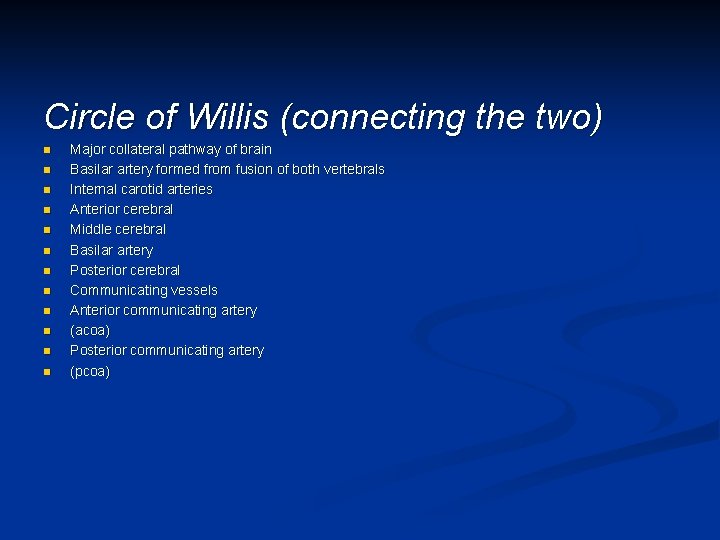

Circle of Willis (connecting the two) n n n Major collateral pathway of brain Basilar artery formed from fusion of both vertebrals Internal carotid arteries Anterior cerebral Middle cerebral Basilar artery Posterior cerebral Communicating vessels Anterior communicating artery (acoa) Posterior communicating artery (pcoa)

Circle of Willis